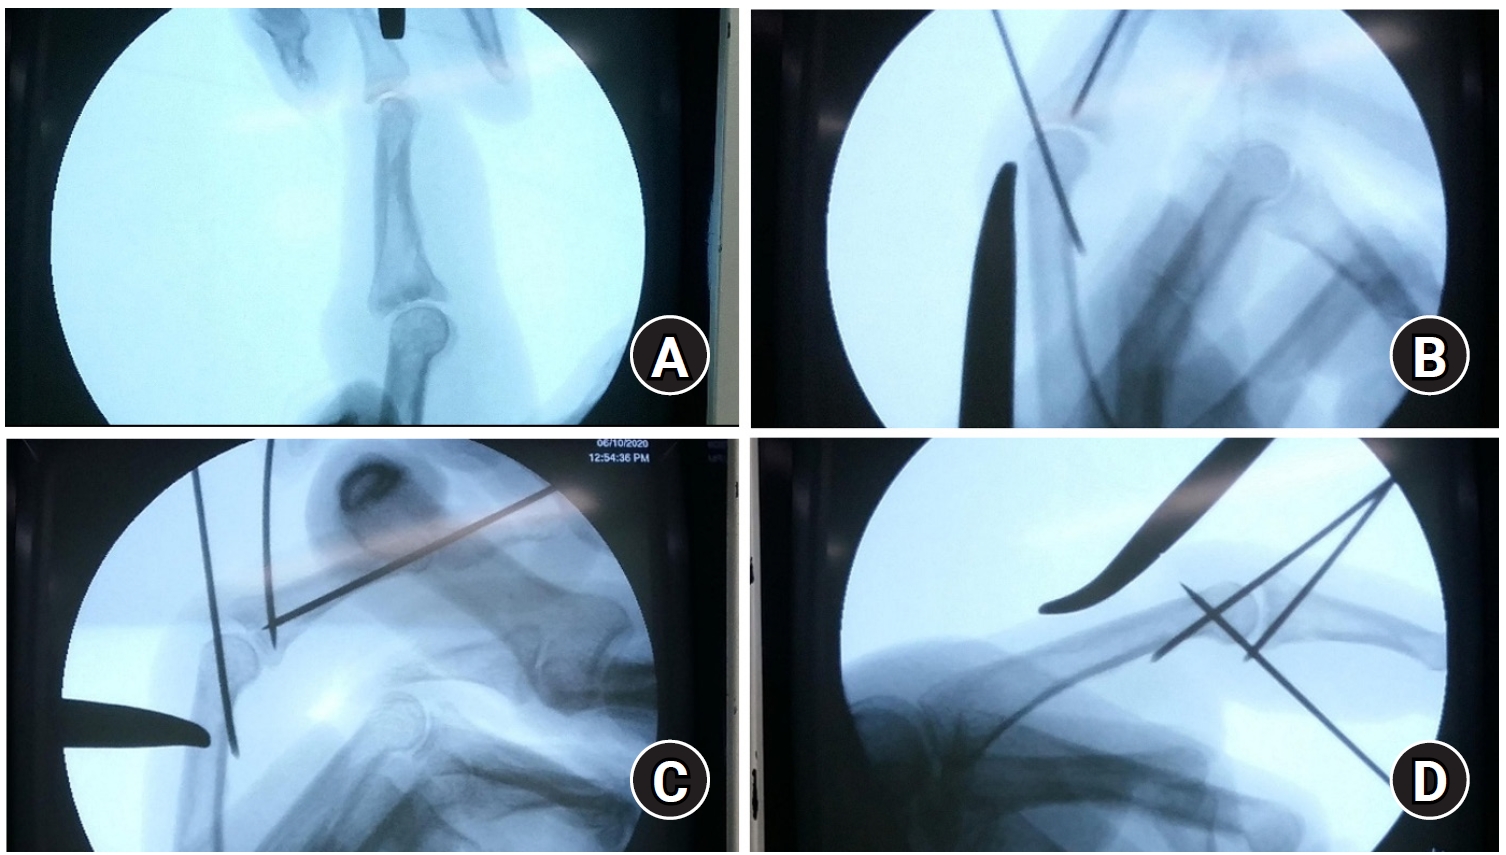

The head of the middle and proximal phalanges are composed of two condyles that form the joint surface at the base of the distal or middle phalanx. The stability of the joint is contributed by the thick palmar plate on the palmar side, the relatively thin joint capsule and extensor tendons on the dorsal side, and collateral ligaments on both sides. Three main types of classification are commonly used based on whether fractures involve the joints and whether displacement occurs [40]. Type I fractures are stable, nondisplaced intraarticular fractures, while type II (unilateral) and type III (bilateral) fractures, which are unstable, require surgical treatment. Depending on the degree of displacement or the size of the fracture fragment, closed or open reduction may be required, and fixation can be achieved using metal pins, mini screws, or headless screws. However, it can be difficult to achieve stable fixation when the fragment size is small, and external fixation may be applied in cases of comminuted fractures or joint instability (Fig. 2).

Fig. 2.

Distraction dynamic external fixator for displaced condylar fracture of the proximal phalanx. Open reduction was required for a displaced articular fracture involving the condyle of the proximal phalangeal head of the fourth finger (A). Due to the presence of small fracture fragments, the fracture was stabilized using a distraction dynamic external fixator and a temporary Kirschner wire (B, C). Bone union was achieved; however, malunion persisted in the coronal plane (D, E). Despite the malunion, there was no functional impairment of hand movement (F, G).

Fig. 2. Distraction dynamic external fixator for displaced condylar fracture of the proximal phalanx. Open reduction was required for a displaced articular fracture involving the condyle of the proximal phalangeal head of the fourth finger (A). Due to the presence of small fracture fragments, the fracture was stabilized using a distraction dynamic external fixator and a temporary Kirschner wire (B, C). Bone union was achieved; however, malunion persisted in the coronal plane (D, E). Despite the malunion, there was no functional impairment of hand movement (F, G).